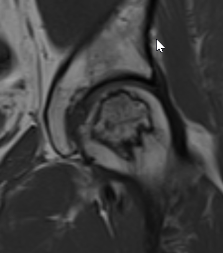

T2 Double Line Sign

Two lines virtually diagnostic of AVN

- outer line / low signa intensity

- inner line / high signal intensity / hypervascular granulation tissue